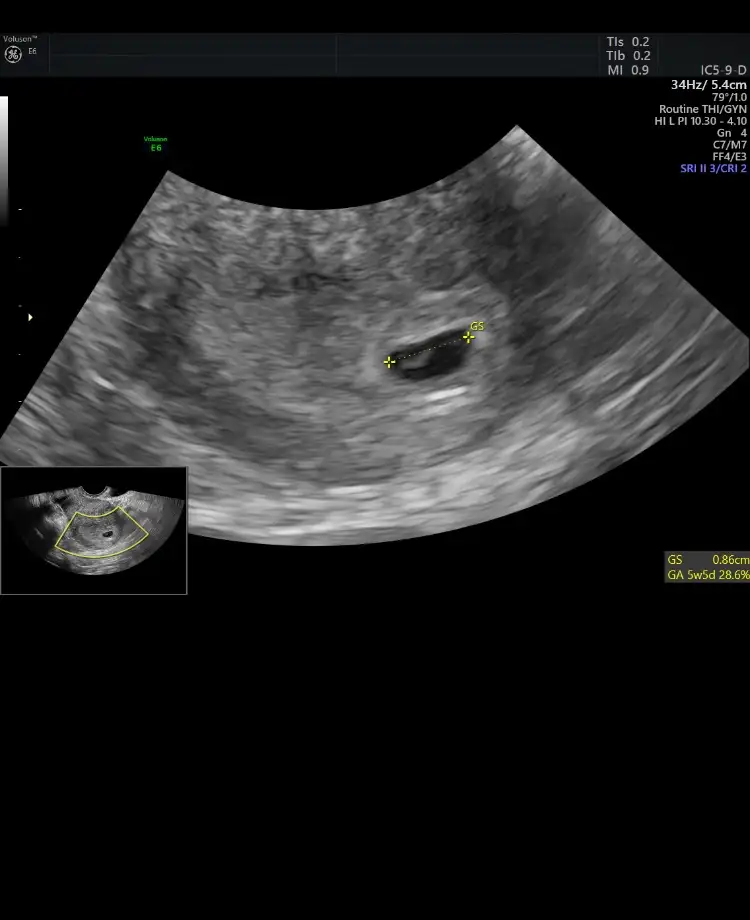

Buna göre erkek en iyi 11 12 13 haftlarIkra meyra Tahminde bulunur musun rica etsem. Karından 7 haftalık ..

Oylemi hayırlısı olsun insallah .Ozaman da paylaşırım tabi. Daha 8 haftalıkBuna göre erkek en iyi 11 12 13 haftlar

Baktım cnm sadece 11 ve 8 haftalık paylaşmışınız. Ve 15 haftalıgıMeraba kızlar bende 8 haftalik görüntü atmıştım tahmin yapan kişi erkek dedi şuan 15 haftaligiz ve oğlum olcak sizede örnek olsun ultrason resmimiz:)

Kız gibi ama en iyi 11 12 13 haftalar olmalıkarından ultroson 8+4 dü o zamanlar. tahminde bulunursanız sevinirim. teşekkürlerIkra meyra